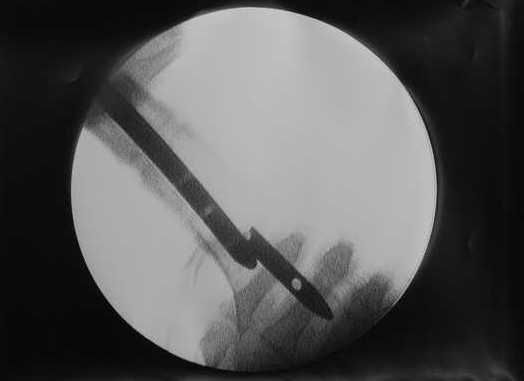

В приложении пример, дистальный отломок пружинил кзади. Два винта потому, что первый оказался чуть кпереди и не упирался в гвоздь.